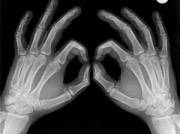

Zrela kost pojavljuje se u dva osnovna oblika, kao kompakta ili kortikalna kost i spongioza ili trabekularna kost, koje se mogu razlikovati golim okom na preseku kosti i na radiografijama. Kompakta se nalazi na površini kostiju i predstavlja gusto, solidno koštano tkivo prožeto mikroskopski vidljivim kanalićima. Najveći deo koštanog tkiva (80%) čini kompakta, dok trabekularna kost učestvuje sa svega 20% u ukupnoj masi tvrde supstance čitavog skeleta.